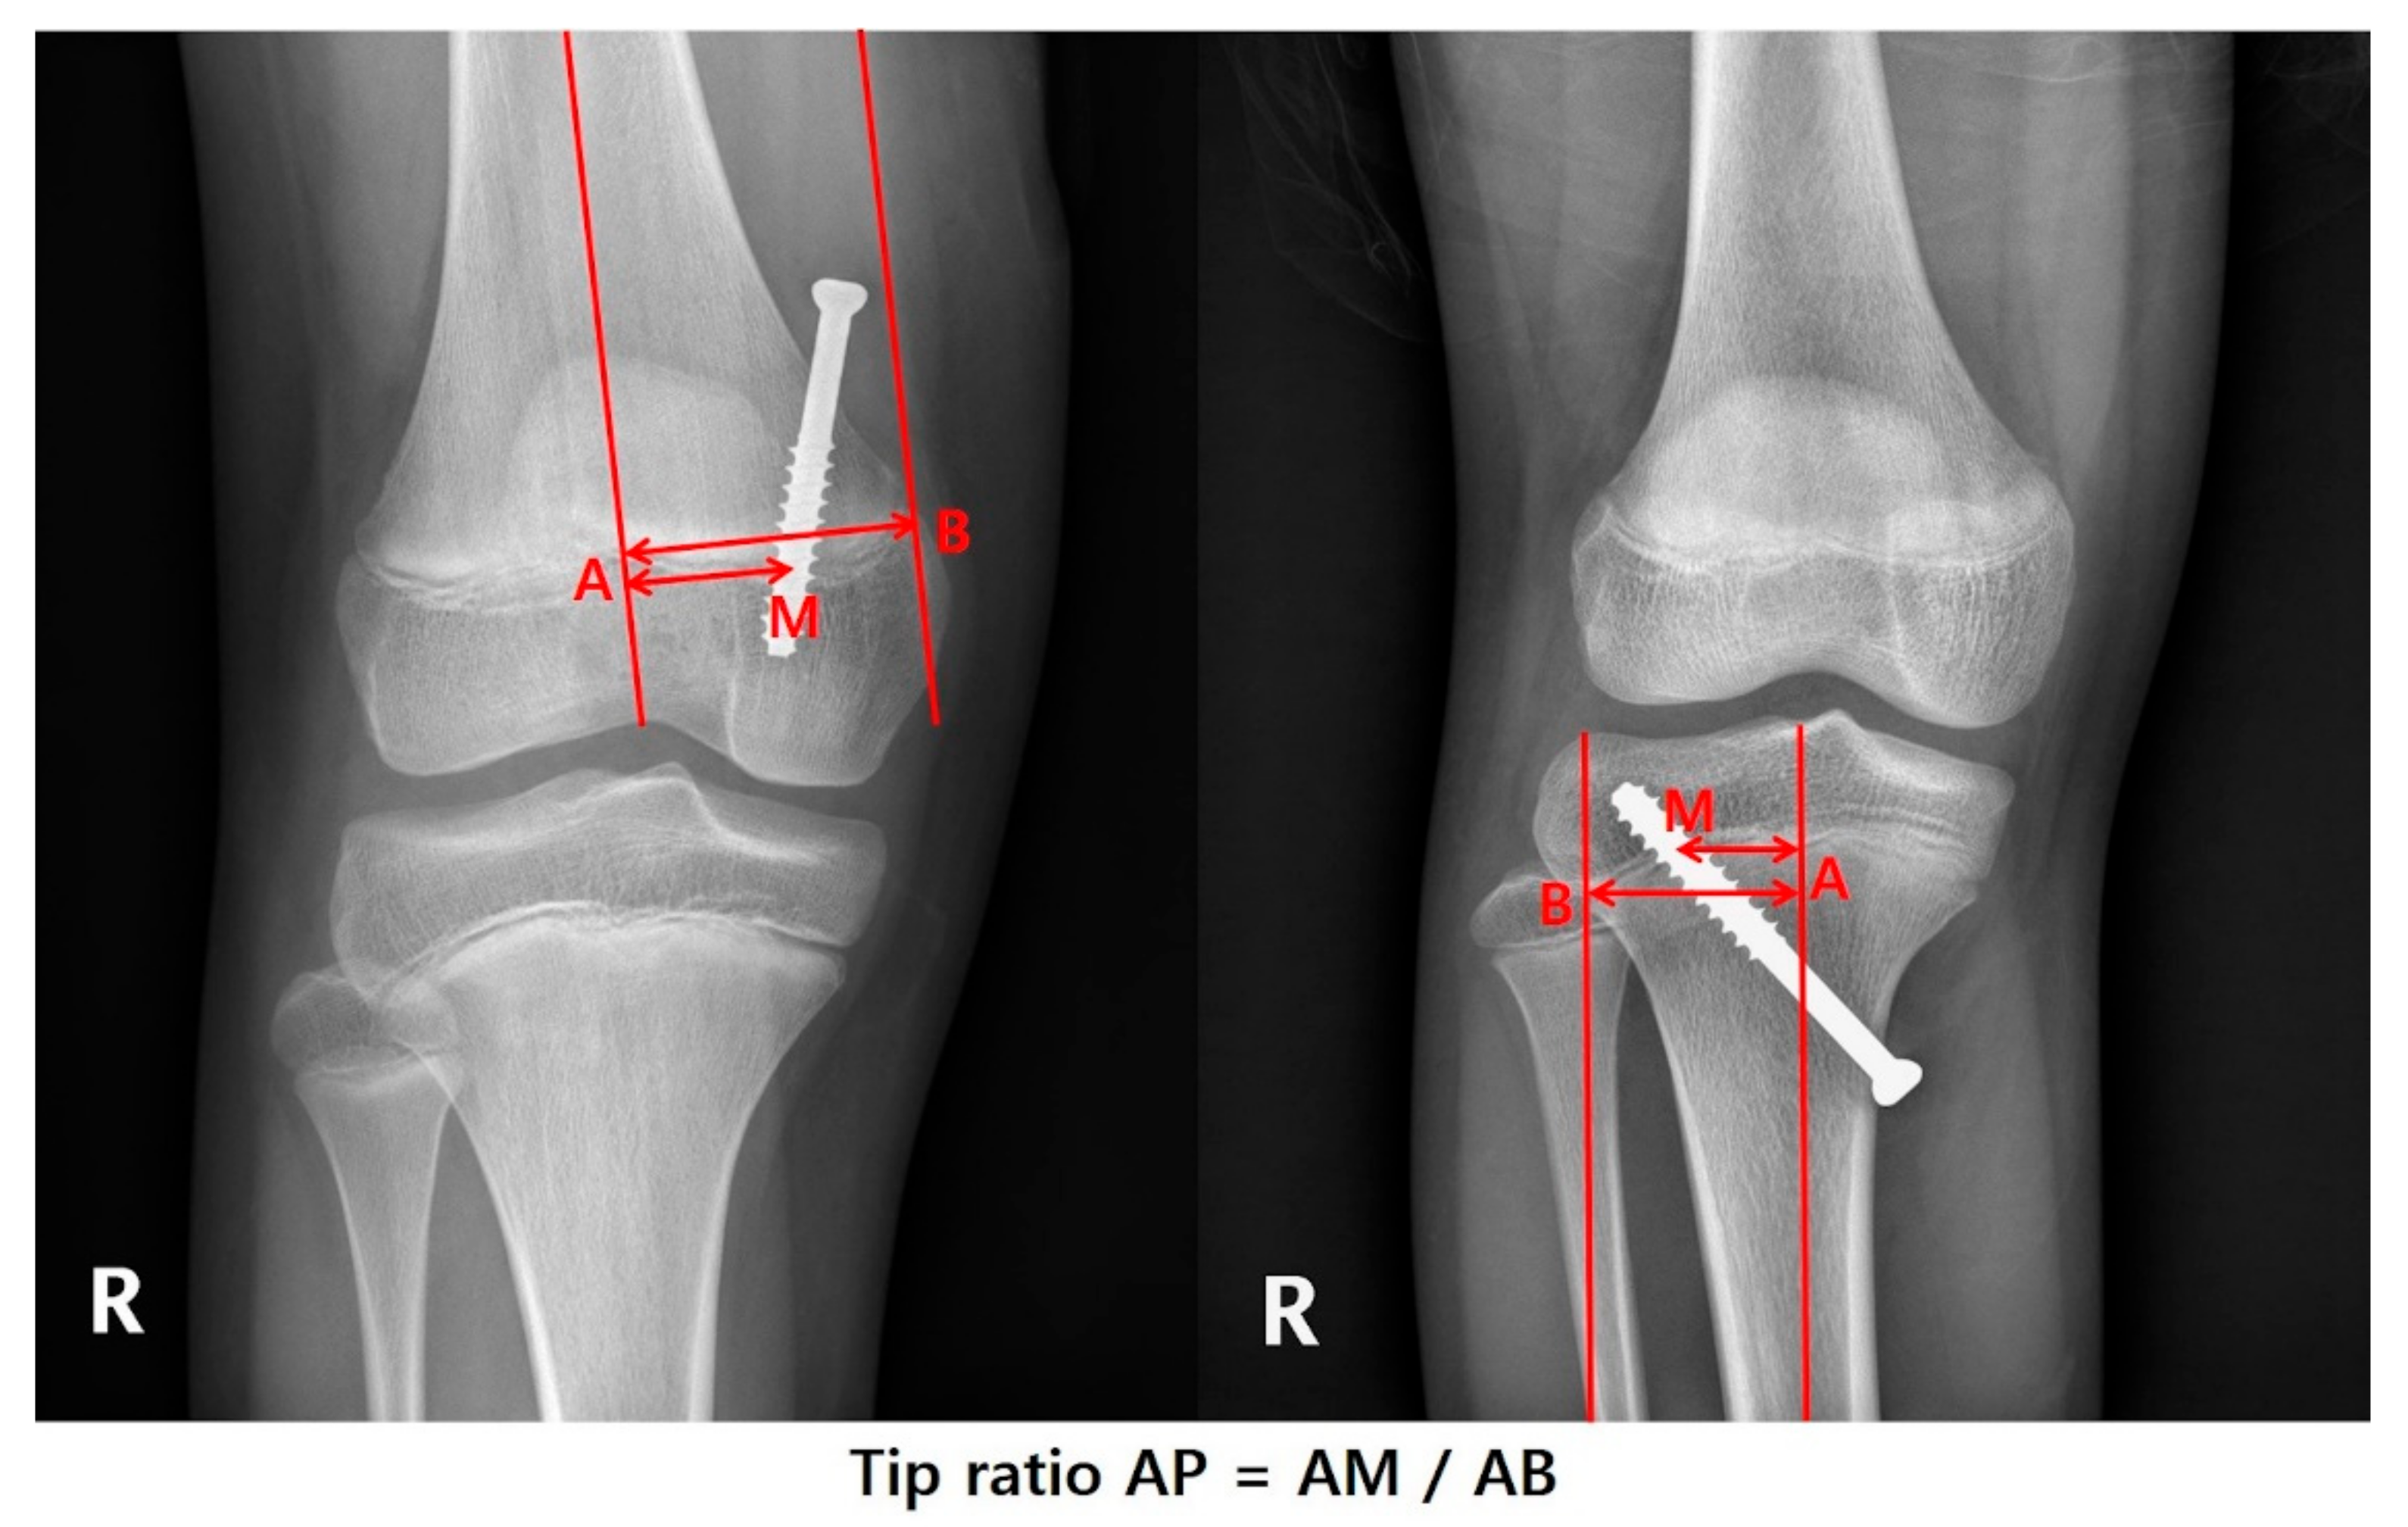

| Tip ratio AP | 0.64 ± 0.1 | 0.64 ± 0.09 | 0.63 ± 0.11 | 0.948 |

| Tip ratio Lat | 0.45 (0.39–0.5) | 0.41 (0.37–0.48) | 0.5 (0.47–0.54) | <0.001 |

| Tip ratio AP | −1.578 (−2.808 to −0.348) | −0.304 | 0.065 | |||

| Tip ratio Lat | −1.313 (−2.250 to −0.377) | −0.329 | 0.008 | |||

| * Tip ratio AP | Valgus | −2.519 (−4.045 to −0.993) | −0.447 | 0.053 | −2.909 (−4.273 to −1.544) | −0.516 | 0.150 |

| ** Tip ratio Lat | Valgus | −0.203 (−1.740 to 1.333) | −0.040 | 0.797 | |||

| Varus | −1.543 (−2.507 to −0.58) | −0.595 | 0.006 | −1.218 (−2.107 to −0.33) | −0.470 | 0.016 | |